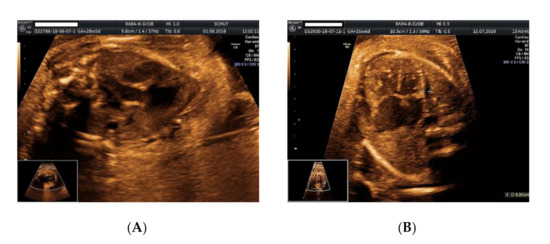

2. Case Presentation